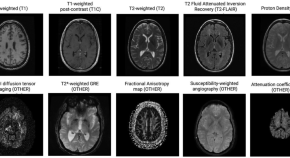

Artificial Intelligence-Powered Clinical Decision Support and Simulation Platform for Radiology Trainee Education